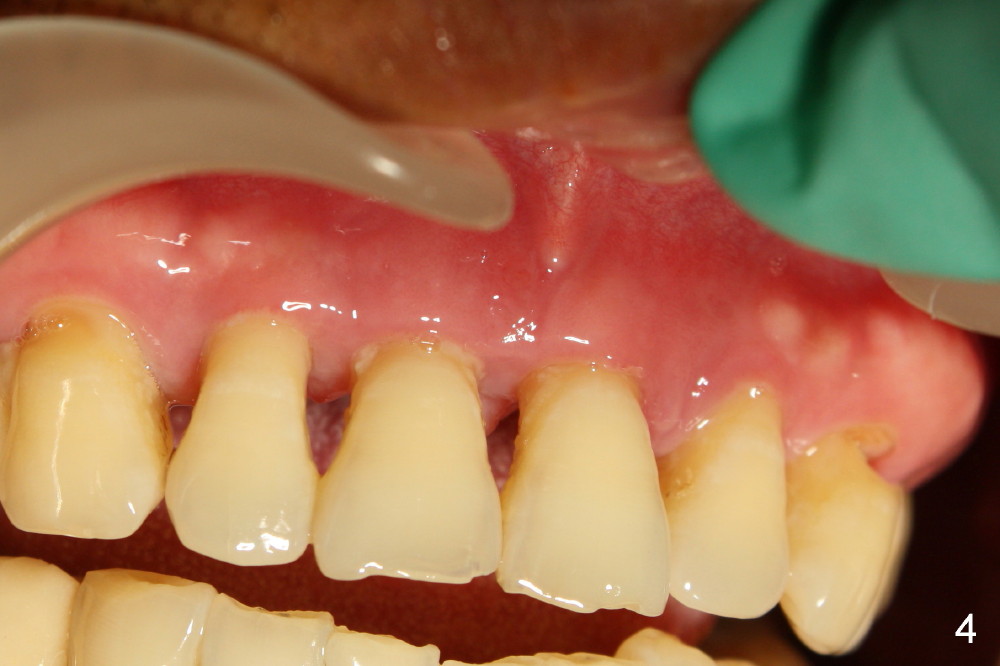

A 44-year-old man has advanced periodontitis (Fig.1,2). The infection resolves substantially 5 days post scaling & root planing (Fig.4,5). The two centrals have severe bone loss (Fig.3) and are going to be replaced by 5x20 mm implants (Fig.6).